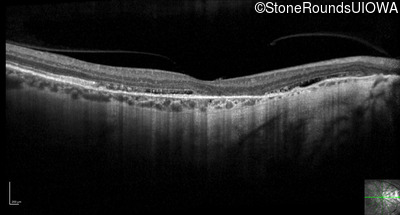

Optical Coherence Tomography - Right - 20/30 +1

Exemplar / OCT Stack